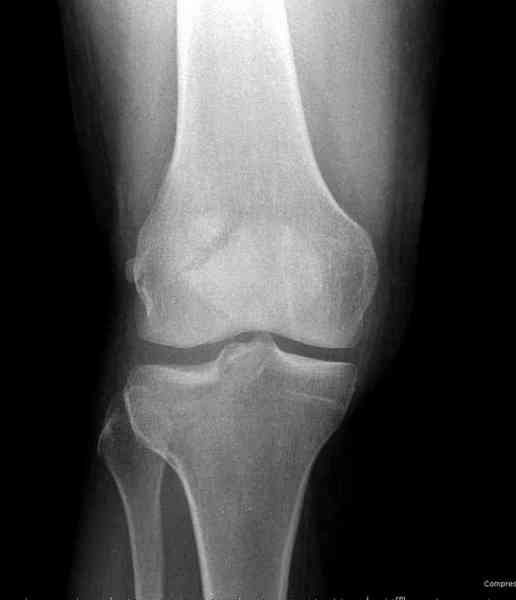

Как всегда прекрасная презентация. Совершенно согласен с необходимостью сохранять мениск и вообще согласен со всем, кроме одного. Фиксация должна проводиться после правильно выполненной репозиции. Главная цель репозиции - это восстановить высоту наружного мыщелка. В норме наружный мыщелок выше внутреннего на 4-5 мм на снимке в переднее заднем направлении АР.

Необходимость репозиции возникает при снижении высоты от 3 до 5 мм по разным источникам. По моему опыту 4 мм. Если не восстановить высоту мыщелка возникает вальгизация коленного сустава с относительным расслаблением передней крестообразной связки. При этом развивается нестабильность коленного сустава из-за недостаточности ПКС.

На представленном после операционном снимке нет репозиции, на что указывает низкое положение тибиального плато и перекрытие кортикальных пластинок в метафизарной части - указано стрелкой. Обычно чрескожную фиксацию я применяю